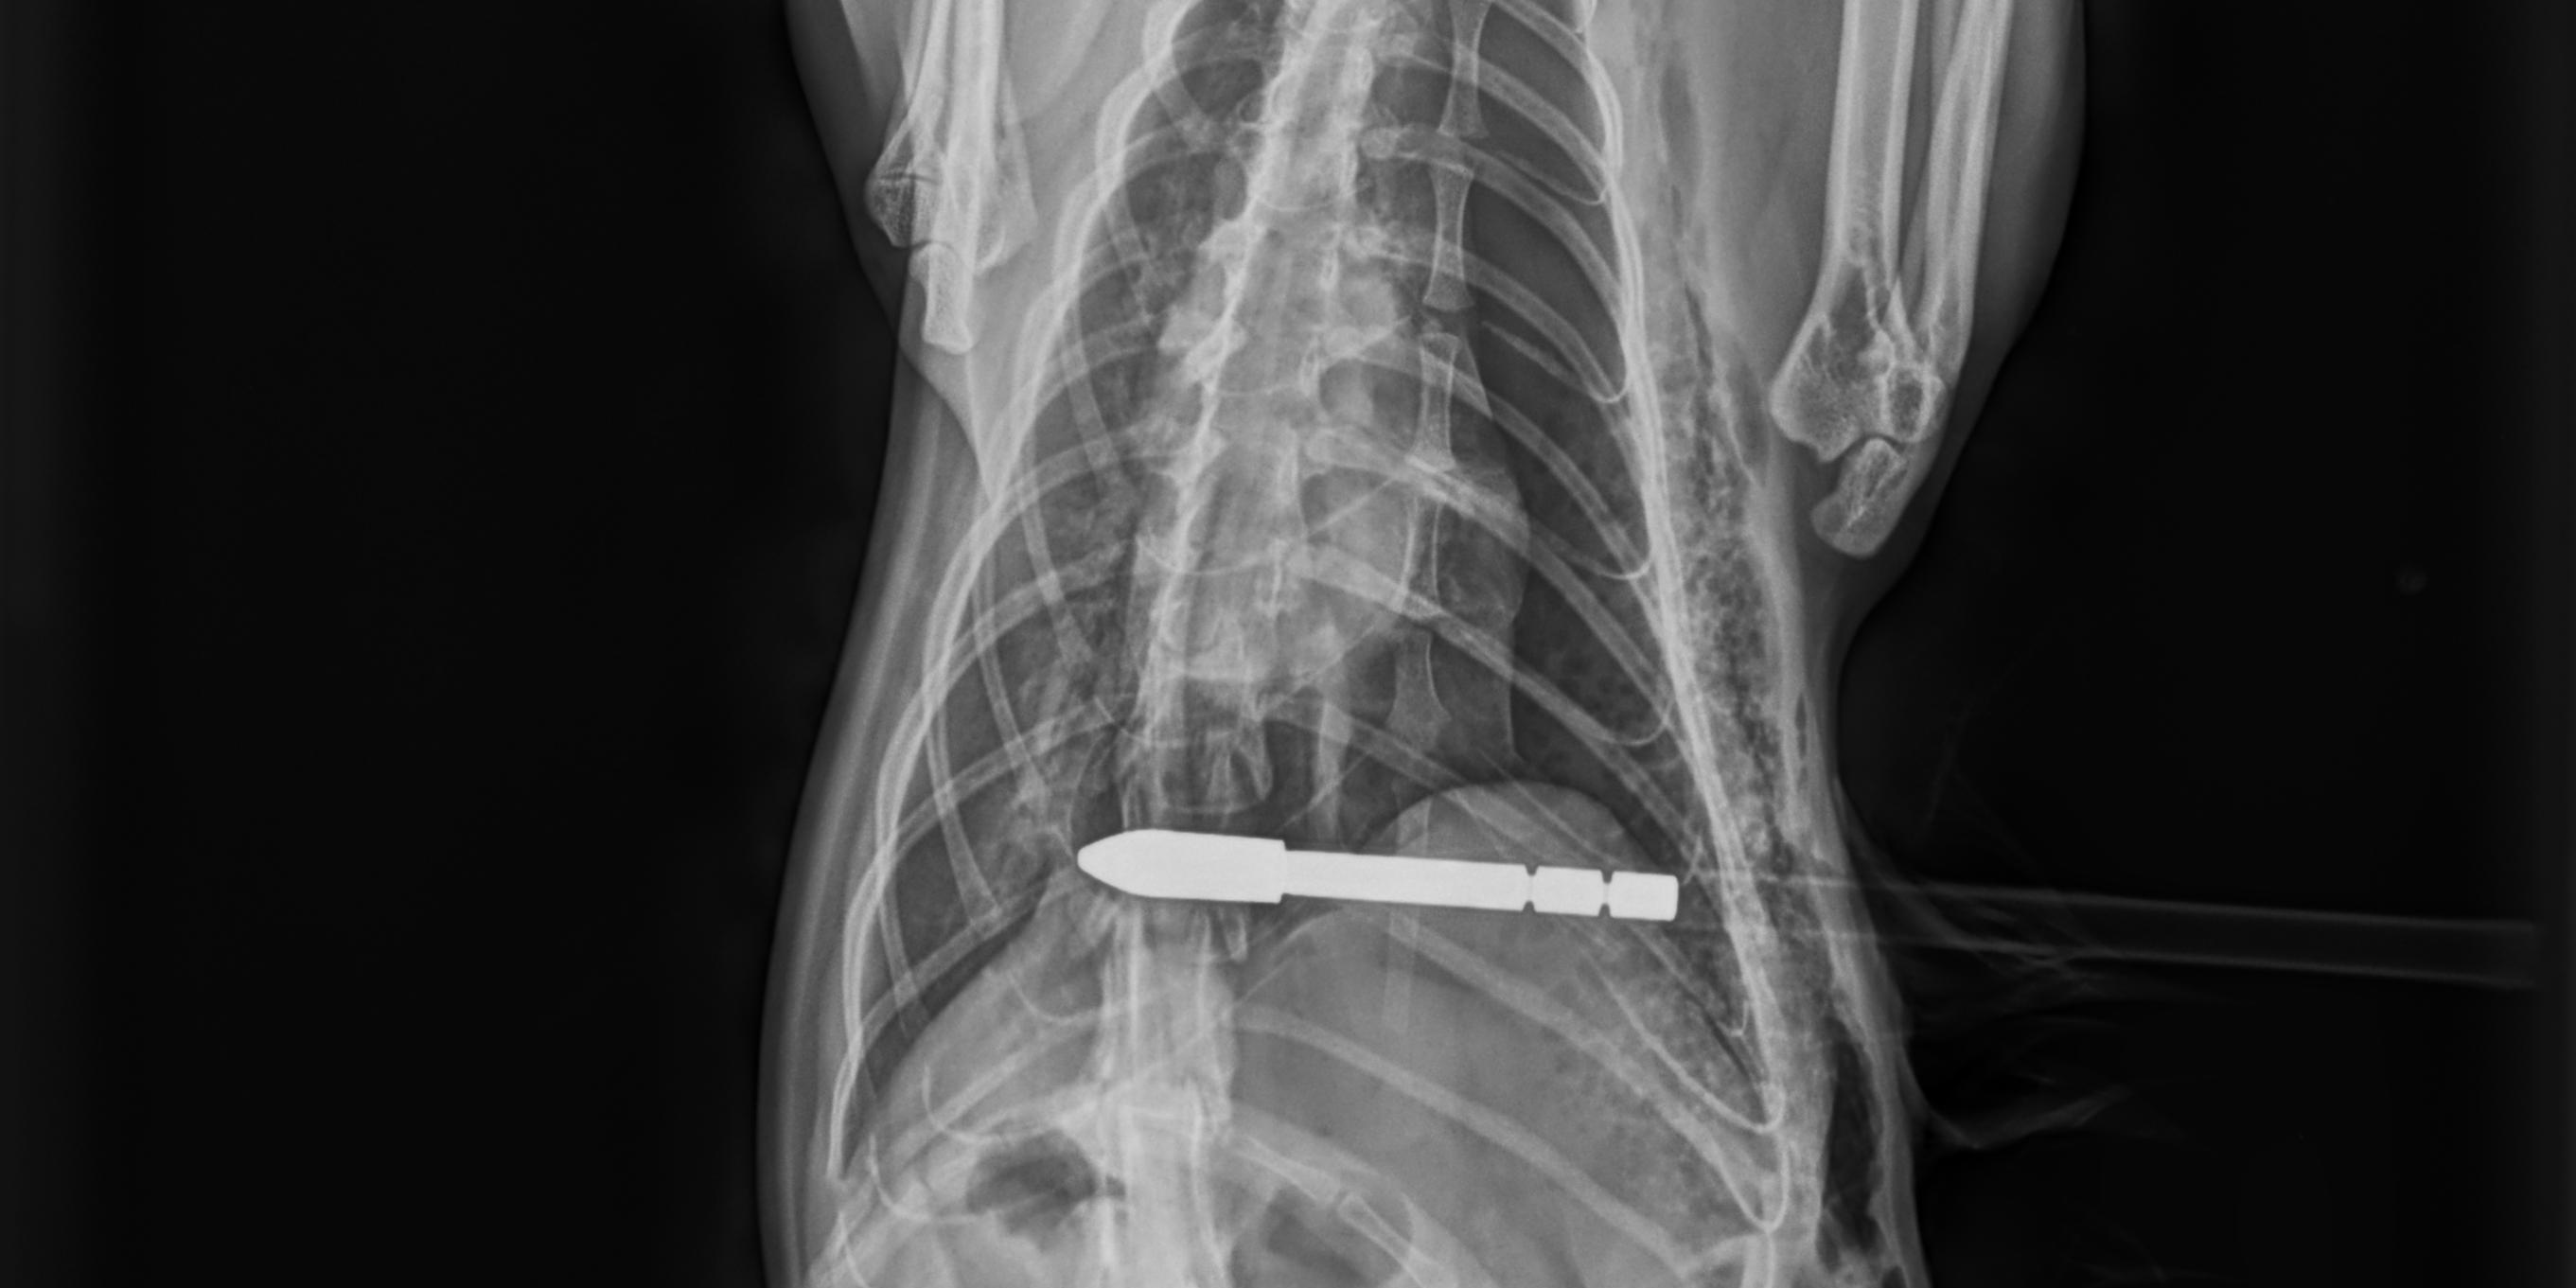

Kärnten. Mittwochnachmittag schoss ein bisher unbekannter Täter im Bereich Zmuln, Gemeinde Liebenfels (Bezirk St. Veit an der Glan) mit einem Pfeil auf eine freilaufende Katze. Der Pfeil durchbohrte die Katze, verletzte diese im Bereich der Lunge und blieb in ihr stecken. Die Katze wurde in eine Tierklinik in Klagenfurt gebracht und der ca. 80 cm lange Pfeil operativ entfernt. Das Tier befindet sich derzeit in äußerst kritischem Zustand.

© LPD Kärnten